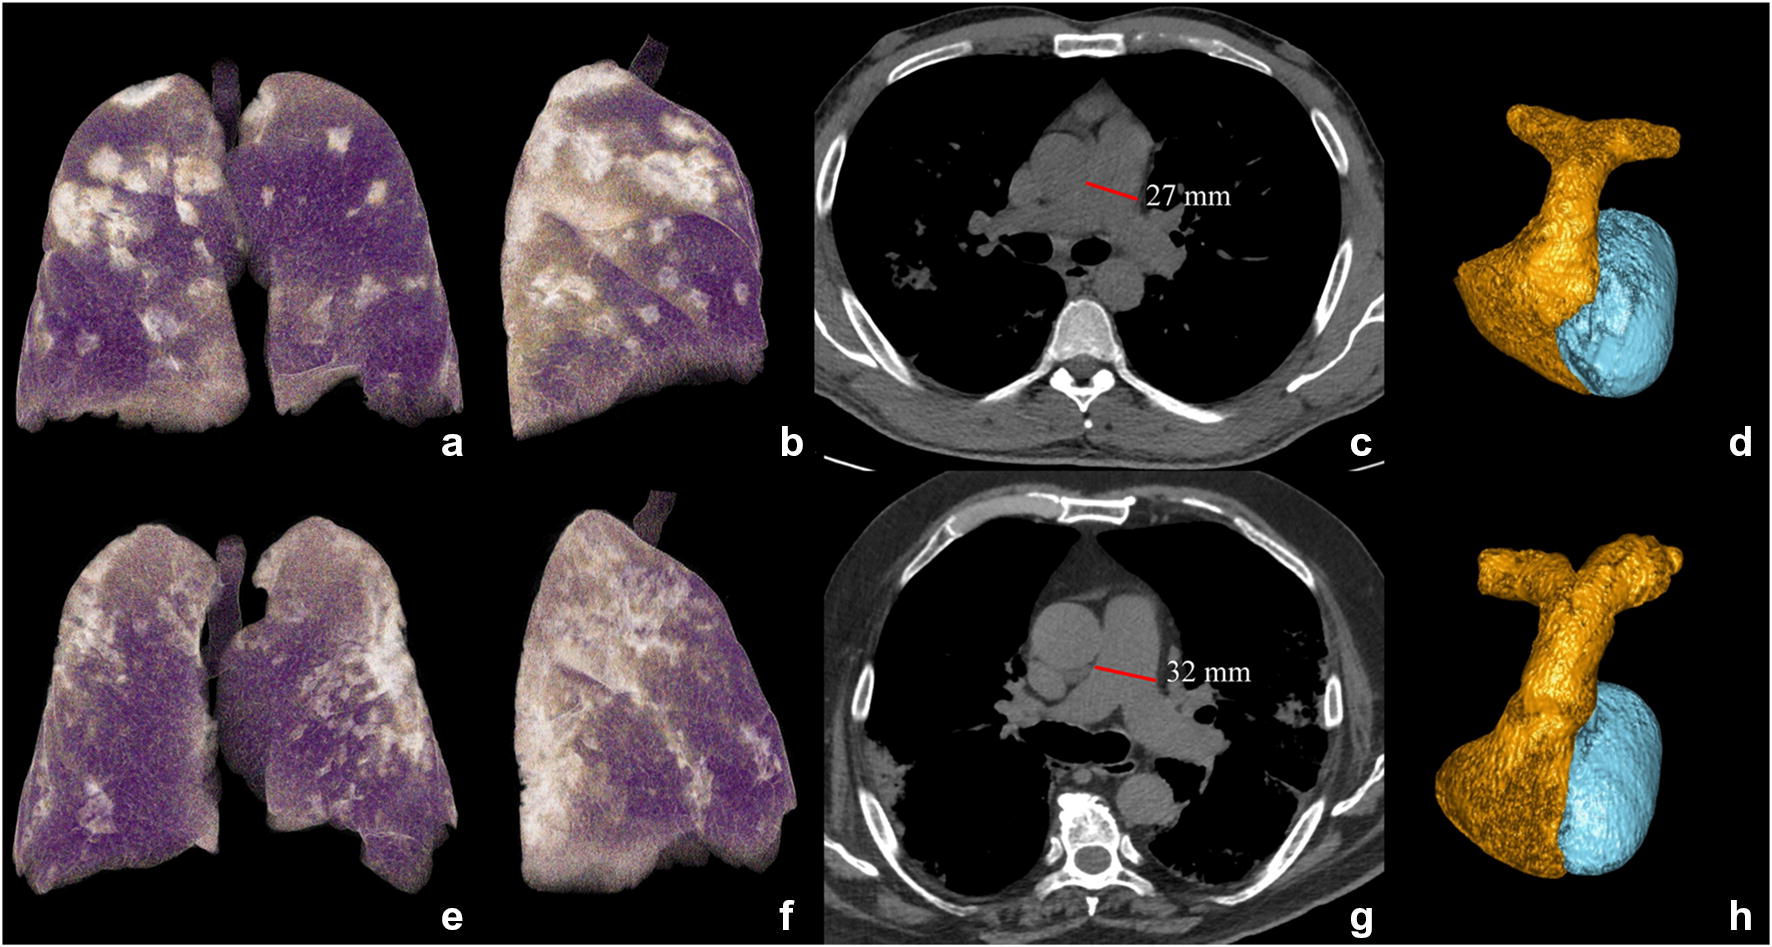

Fig. 4

Exemplifying cases: a survivor (top) and non-survivor (bottom) patients. CT 3D volume rendering of lungs in antero-posterior view (a, e) and lateral view (b, f), CT axial images with mediastinal window (c, g) for main pulmonary artery diameter (MPAD) measurement (red lines in c, g), and 3D volumetric reconstruction of pulmonary arteries (d, h) in a survivor (top) and a non-survivor (bottom) COVID-19 patient, both males of 74 and 76 years, respectively, both with history of hypertension and treated ischemic cardiomyopathy, both suffering from fever (> 37.5 °C) and caught from 7 days. At the admission, WBC/mm3 were 4.36 and 3.8, CRP 0.93 and 1.1 mg/dL, LDH 295 and 378 U/L, and creatinine 0.93 and 1.1 mg/dL in survivor and non-survivor, respectively. The oxygen saturation was 90% and 94% for survivor and non-survivor, respectively, with higher well-aerated lung volume in the survivor patient (3882 mL vs 2382 mL, violet parenchyma on 3D lung volume rendering in a, b, e, f) with pneumonia (bright parenchyma in a, b, e, f), involving from 25 to 50% of lung volume in both cases. Pulmonary artery diameter was normal (27 mm) in the survivor (c, d) while it was enlarged (32 mm) in the non-survivor (g, h) who died 9 days after hospital admission